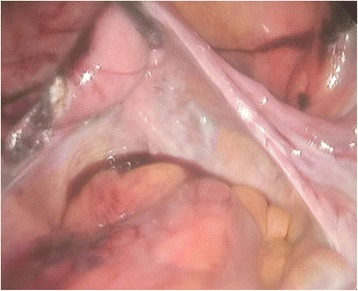

A 77-year-old Korean woman, gravida 5, para 5, was admitted through the emergency room because of lower abdominal pain, poor oral intake, and a recent increase in abdominal size for 4 days. The symptoms had gradually increased in severity. She had no history of acute pain or previous operation. Abdominal examination revealed tenderness and rebound tenderness of the lower abdomen with a palpable mass in the left lower quadrant. Ultrasound examination showed an enlarged left ovarian cyst measuring 14.3 × 14 × 8.6 cm with diffuse internal echoes, including a 6.1 × 6.0 cm hypoechogenic component without significant vascularity. The right ovary was not seen and the uterus was normal and atrophied. Contrast-enhanced computed tomography (CT) revealed an approximately 12-cm well-circumscribed mass (of fat and soft tissue density) in the pelvic cavity and a 9-cm well-circumscribed mass (of fat and soft tissue density) with calcification in the right subhepatic space (Fig. 1). The suggested preoperative diagnosis was benign teratoma of the left ovary and right subhepatic space. With regard to preoperative examination, the laboratory tests, biochemical tests, complete blood counts, blood coagulation profile, and urinalysis were all normal. The C-reactive protein (CRP) level was elevated at 6.87 (normal range 0–0.3 mg/dL), CA-125 was elevated at 50.76 (normal range 0–35 U/mL), and CA 19-9 was normal at 22.06 (normal range 0–37 U/mL). We decided to proceed with laparoscopy. Laparoendoscopic single-site surgery (LESS) was performed through a 20-mm intraumbilical incision using a Glove port (NELIS, Bucheon, South Korea). During laparoscopy, torsion of the left adnexa due to an approximately 12 × 10 cm left ovarian cyst was visualized, with an atrophied normal uterus. The left adnexa was rotated 1440° clockwise with multifocal purple discoloration and severe adhesion to the sigmoid colon (Fig. 2). The right ovary and tube could not be identified in the proper anatomical location (Fig. 3). A second cystic mass of about 10 × 7 cm was noted in the right subhepatic space. It was surrounded by thin filmy adhesions to the omentum, bowel, and appendix (Fig. 4). Left adnexectomy, intra-abdominal mass excision, and appendectomy were performed by LESS. The abdominal mass was carefully dissected from the surrounding omentum and bowel using a monopolar hook dissector and harmonic scalpel (Ethicon, Somerville, NJ, USA). There was no pedicle that needed to be clamped and no identifiable blood supply. The mass was removed intact. The entire specimen was removed through the umbilical incision without leakage of content using an EndoBag (LapBag, Sejong Medical, Paju City, South Korea). The patient recovered uneventfully and was discharged 4 days after surgery. The histopathological examination confirmed MCTs in the left ovary and right subhepatic space. The abdominal mass included ovarian tissue. These findings could also be interpreted as an autoamputation of the adnexa due to torsion of a previous ovarian cyst arising from the right ovary.

Fig. 3.

Laparoscopic findings. The right ovary and tube are absent